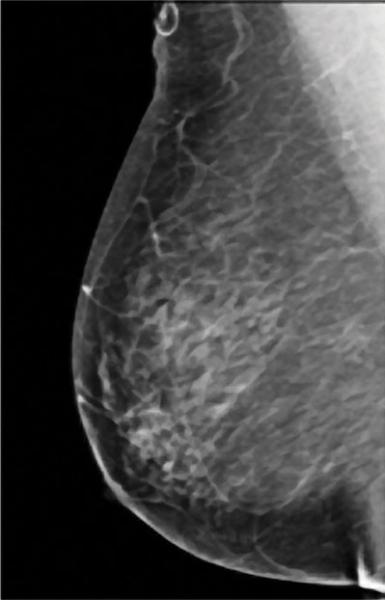

A comparision of a small breast cancer found in a patient without dense breast tissue (left), and a tumor found in a woman with dense fibroglandular tissue. For more information visit DenseBreast-info.org.

Roughly 40 percent of women of mammographic age (40 and older) fall into the last two categories, which are collectively considered dense. As density increases, it becomes more difficult to distinguish tumors and other masses from the surrounding tissue. Apart from this masking effect, dense breast tissue is itself a risk factor for developing breast cancer. Statistical evidence indicates that women with dense breasts are four to six times more likely to develop breast cancer than women with fatty tissue; they are also 17 times more likely to develop interval cancer (detected or presenting less than 12 months following a normal mammogram).